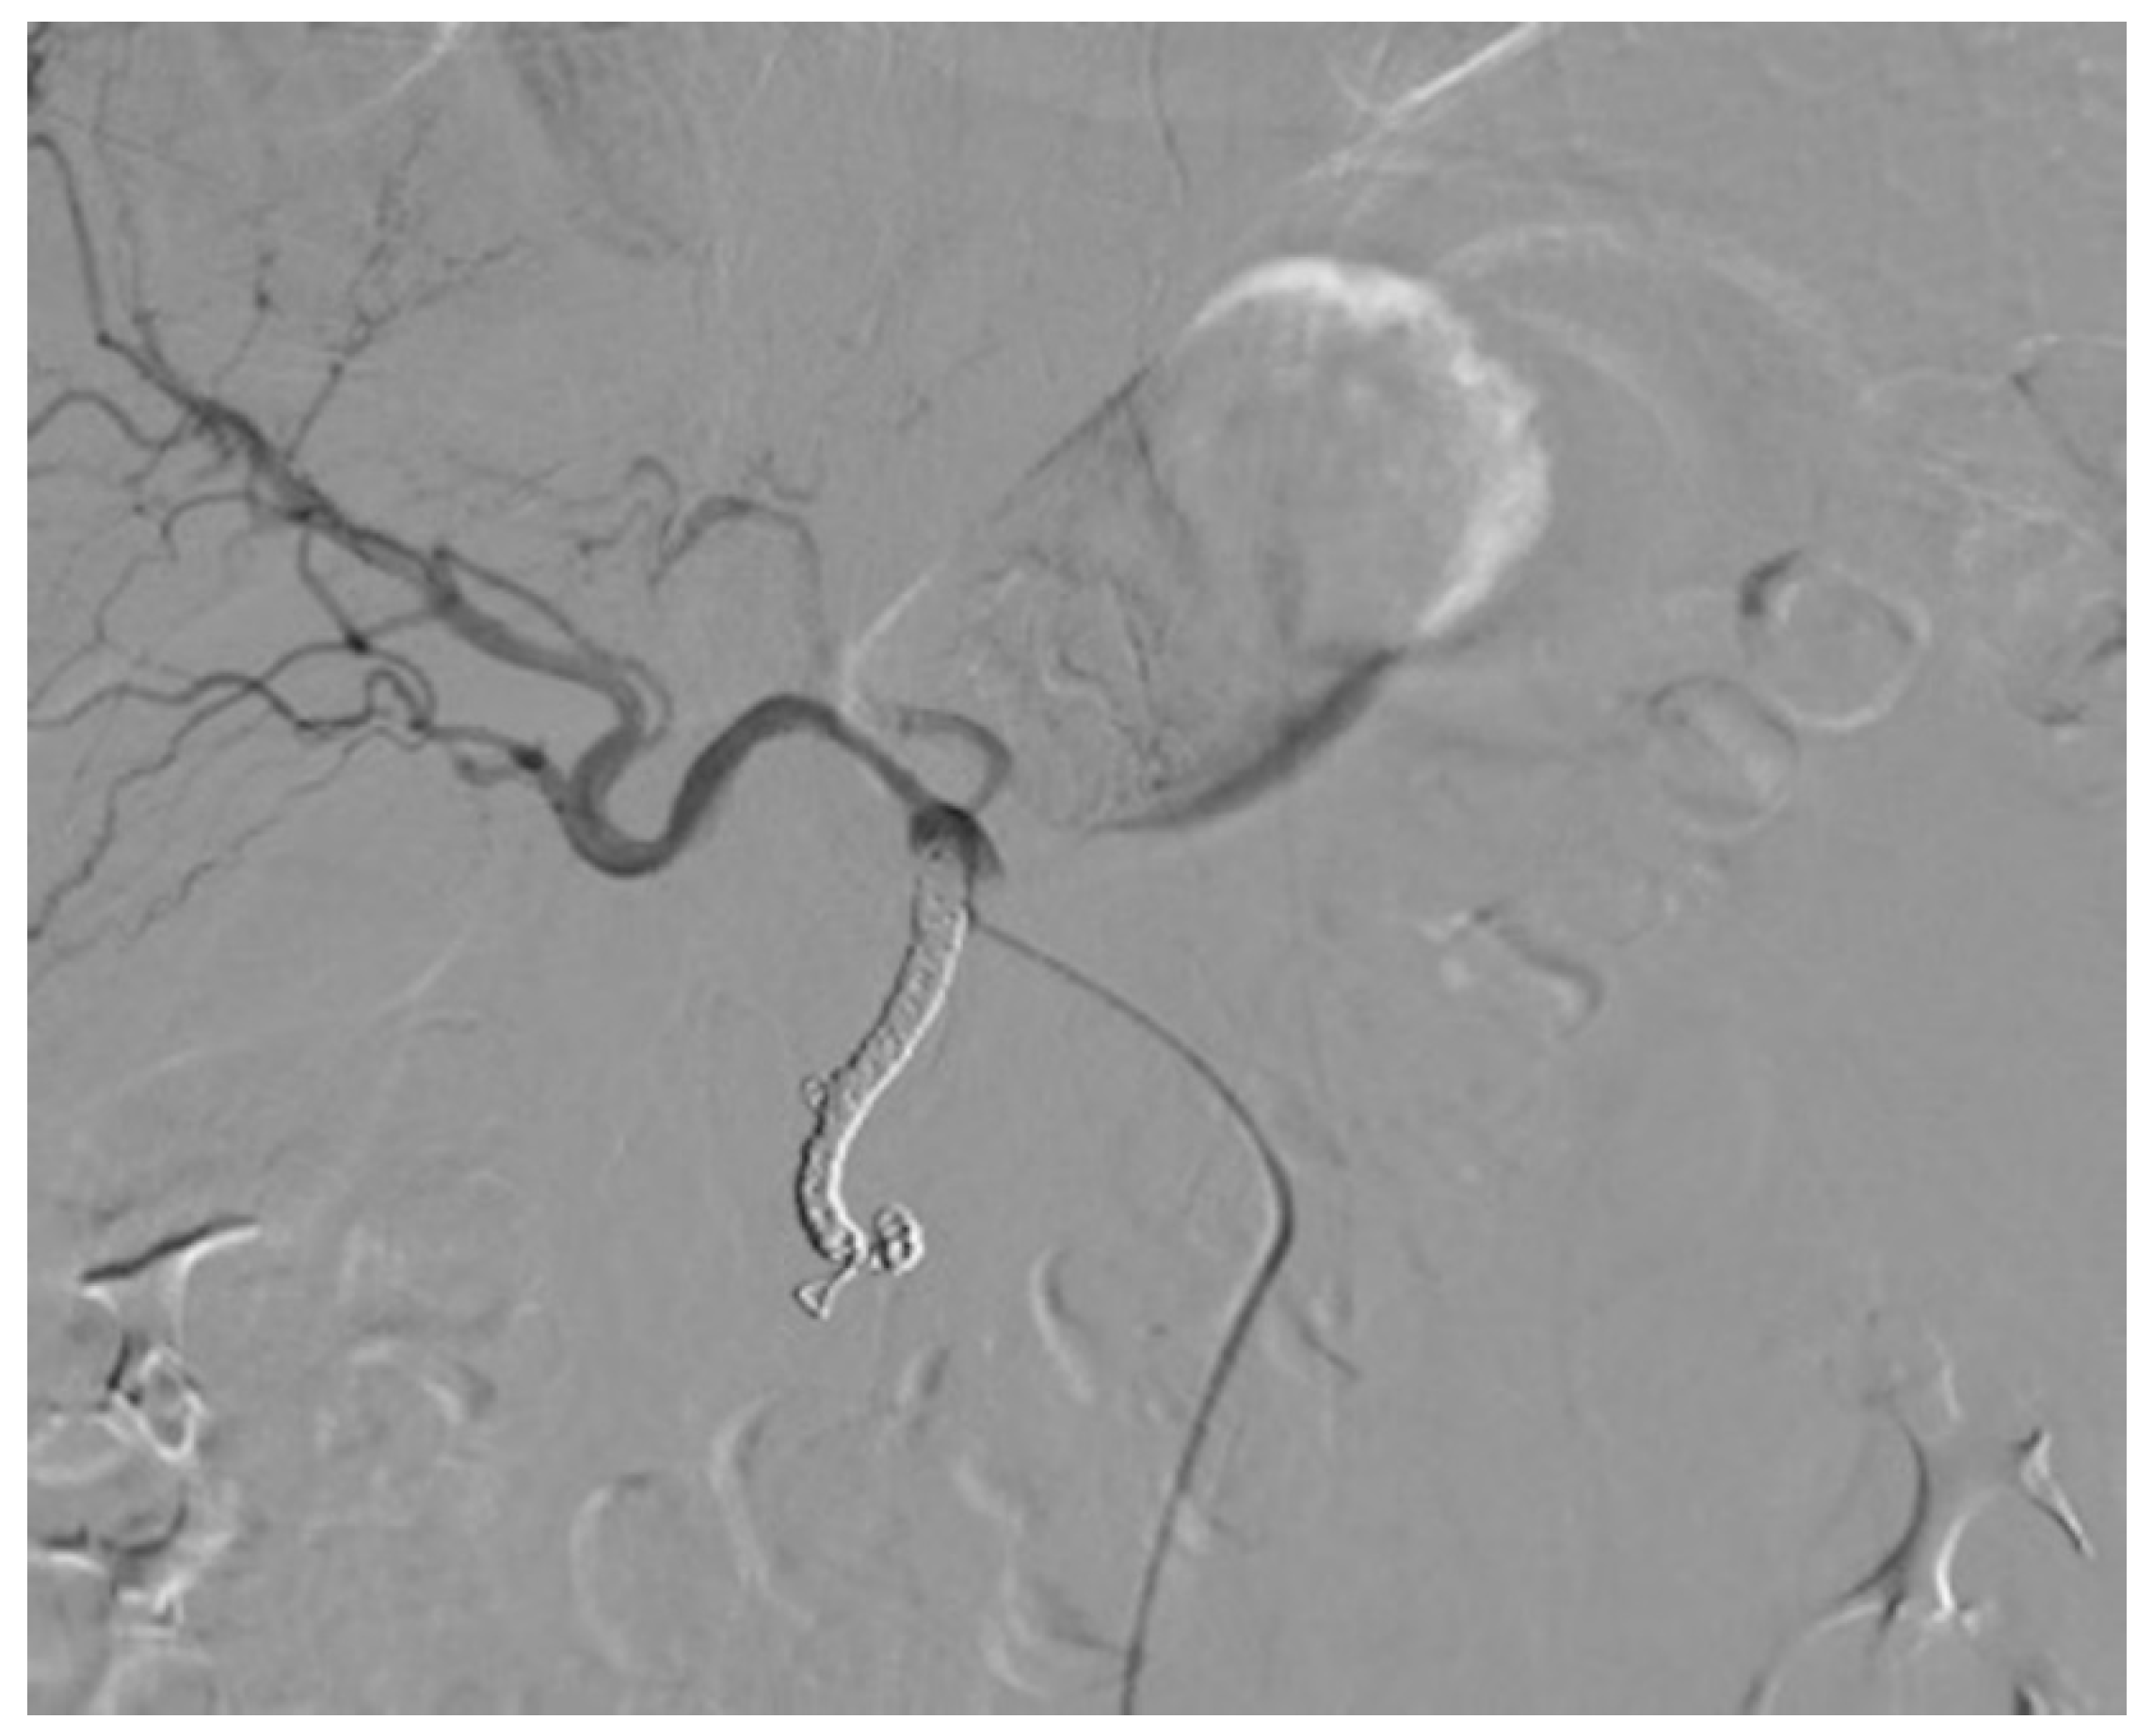

2.2. Percutaneous Microcatheter-Port System Implantation

3.2. Primary Technical Success